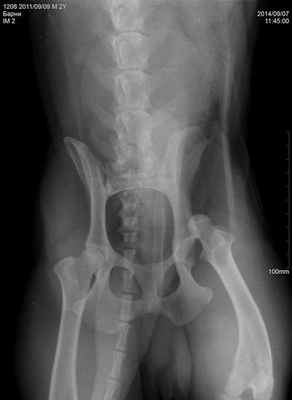

Несмотря на характерные клинические симптомы, для подтверждения диагноза врач обязан сделать рентгеновские снимки в латеральной и вентродорсальной проекциях. Это позволит: подтвердить диагноз, определить направление вывиха, установить отсутствие или присутствие авульсии на месте крепления круглой связки, оценить состояние костей таза, вертлужной впадины, большого вертела бедренной кости и крестцово-подвздошного сустава (Журавков А.А., 2014). Лечение вывиха тазобедренного сустава может быть как консервативным, так и хирургическим. Консервативное лечение вывиха заключается в его закрытой репозиции под седацией и наложением иммобилизирующей повязки. Такой способ лечения допустим при вправимых вывихах, которым не более 2-3 суток. Как правило, по статистике ветеринарной клиники «Самарская Лука», консервативное лечение эффективно не более чем в 25% случаев. В остальных случаях применяется хирургическое его лечение, методов и способов его коррекции в настоящий момент множество.

Травматический вывих тазобедренного сустава у шарпея. Открытое вправление вывиха созданием искусственной круглой связки